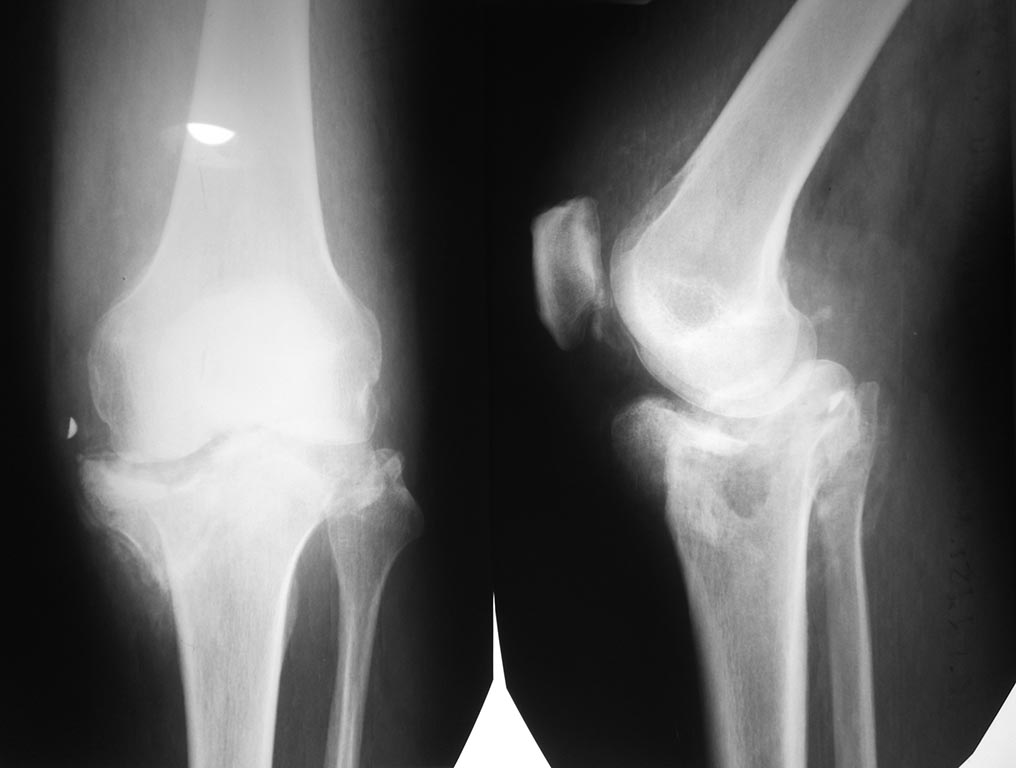

Пациент мужчина, 46 лет, гражданин Украины, рост 170, вес около 70-74. Работал до травмы и в настоящее время, средние физические нагрузки.Травма в декабре 2014, со слов выставил прямую ногу вперед во время катания на велосипеде, факту травмы не придал значение вплоть до моего осмотра (апрель 2015), лечил ушиб. Рентгенограммы (1) январь 2015 год, (2) 25.05.2015 г.

Диагноз: Застарелый многооскольчатый (С3) перелом проксимального отдела ББК.По срокам после травмы (более 6 мес): Ложный сустав (неоартроз) проксимального отдела ББК.